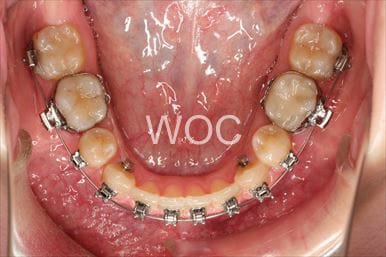

治療中1

治療中2

治療中3

治療中4

治療中5